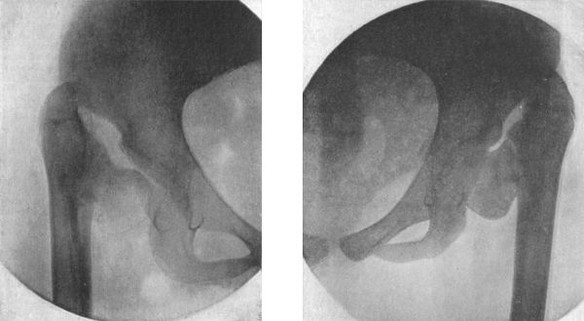

153 80.Section of Knee-joint showing Extent of Synovial Cavity

156 81.Extension applied by means of Ice-tong Callipers for Fracture of Femur